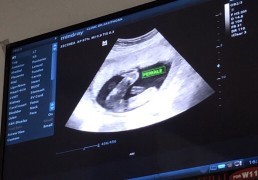

20W หนูเป็นผู้หญิงคะ

Post reply image